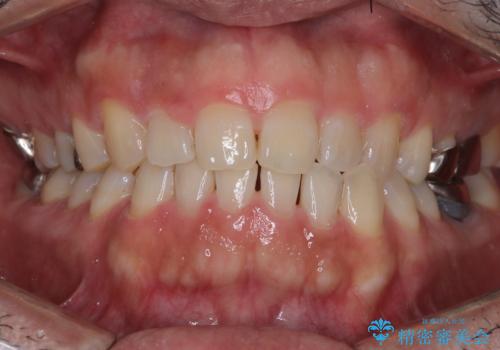

前歯の突出を防ぎながらガタつきを解消。上下左右4番抜歯による審美ワイヤー矯正

担当医 河口智英